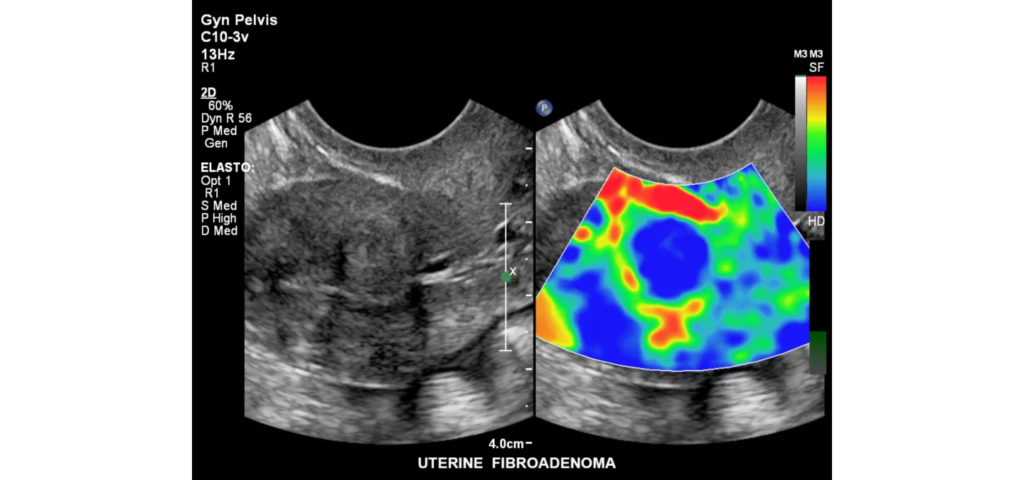

Philips EPIQ Elite ultrasound features an exceptional level of clinical performance, workflow, and advanced intelligence to meet the challenges of today’s most demanding practices. The EPIQ Elite platform brings ultimate solutions to ultrasound, with clinically tailored tools designed to elevate diagnostic confidence to new levels.